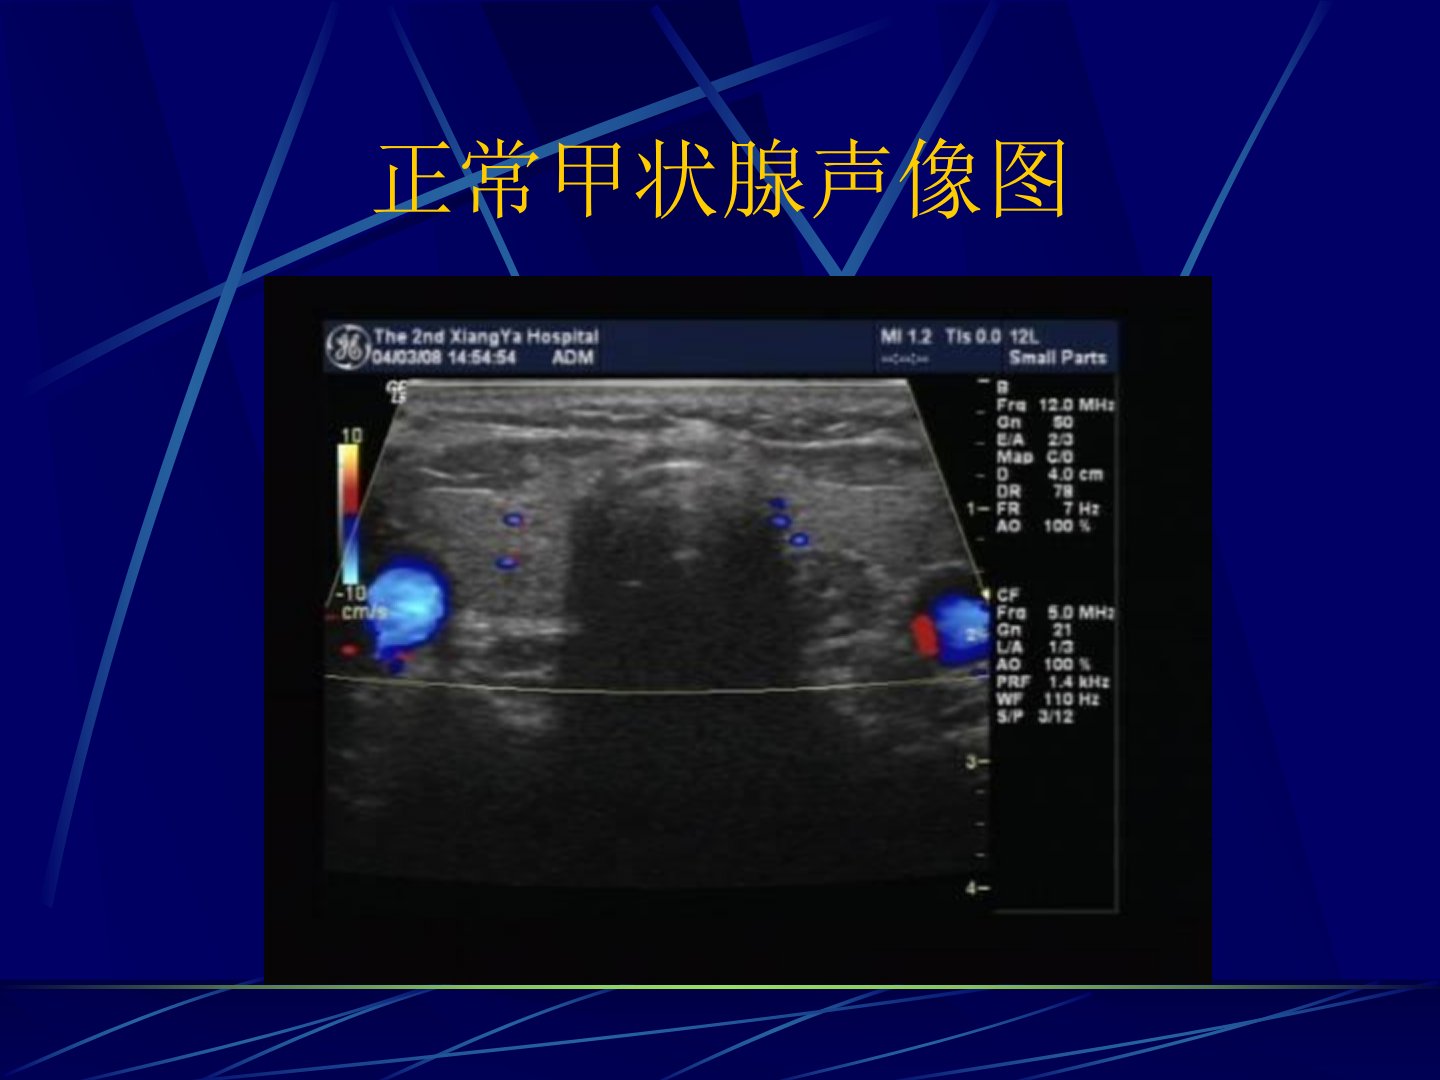

作为医生对7512MHZ声像下亚急性甲状腺炎的特点总结如下:亚急性甲状腺炎在声像图上呈现出明显的特征。其中甲状腺会出现中度增大导致颈前间隙消失。在声像中可见低回声区即所谓的“冲洗征”这是该病症的一个典型表现。病灶的形态往往不规则回声多不均匀与正常的甲状腺组织形成鲜明对比。此外这种病症的病灶多无包膜和晕圈显示出其侵袭性的特点。值得注意的是在声像图中还可能观察到钙化现象即“沙粒体”的出现这进一步支持了亚急性甲状腺炎的诊断。准确识别这些声像特点对于临床医生及时、准确地诊断亚急性甲状腺炎具有重要意义。